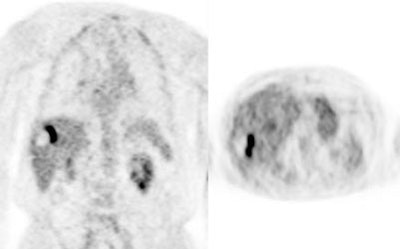

Initial staging for extrahepatic metastases: The patient below underwent FDG PET imaging to assess for extrahepatic metastatic disease prior to definitive surgical intervention. The PET exam demonstrates uptake within two hepatic metastases (black arrows on PET scan and yellow arrows on CT images) and in the patients primary colon cancer (blue arrow on PET scan and white arrow on CT image). No other sites of abnormal tracer uptake were identified which supports surgical intervention in this case. |